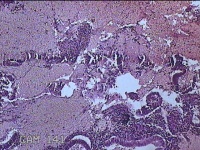

宫腔内容物

性别

女

年龄

50岁

临床诊断

异常子宫出血 子宫腔赘生物待查 子宫肌瘤 疤痕子宫

一般病史

不规则阴道流血25Tina,增多7天。

标本名称

大体所见

灰白暗红色不规则碎组织2.5x1.7x0.8cm一堆。